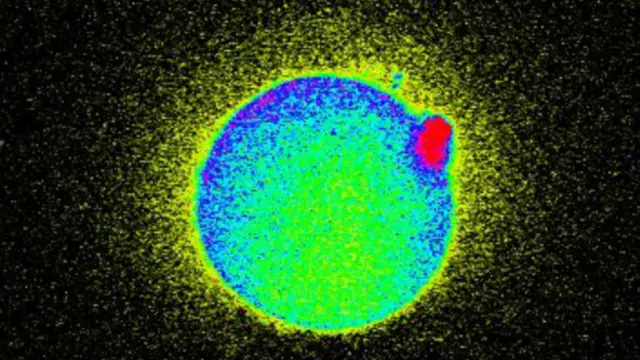

Utilizando un microscopio fluorescente, los investigadores pudieron filmar la luz que se emite durante la fecundación.

Para lograr ver estas chispas, el equipo de investigadores activó la célula sexual inyectando una enzima de esperma que activa el calcio que aumenta el tamaño del óvulo y libera el zinc que vemos en la imagen.

"Estos estudios de microscopía fluorescente establecen que en la biología del óvulo humano también ocurren chispas de zinc, y se pueden observar fuera de la célula", dijo por su parte el profesor Tom O'Halloran, del Instituto de Química de Procesos de Vida de la Universidad Northwestern.